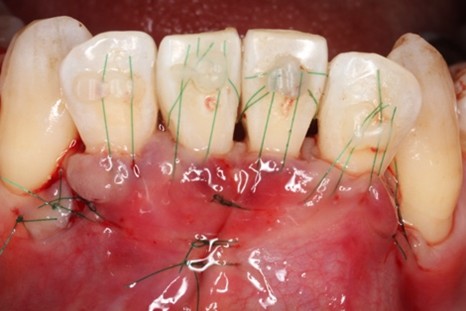

下顎前歯歯肉退縮に対する歯肉移植術の症例紹介

Before

下顎前歯に顕著な歯肉退縮を認める

治療中

切開はEPPT(entire papilla preservation technique)

下の前歯が冷たいものがしみる

歯周基本治療後に根面被覆術を実施しその後はメンテナンス

歯肉退縮が生じることで知覚過敏に繋がるケースは少なくない。また将来的には根面う蝕の可能性も高くなるため、歯肉退縮している場合には予防的な観点から根面被覆手術をした方がいい場合がある。特に知覚過敏が強い場合にはブラッシングがしづらい場合も多くよりう蝕や歯周病のリスクが上がるため注意が必要と考える。